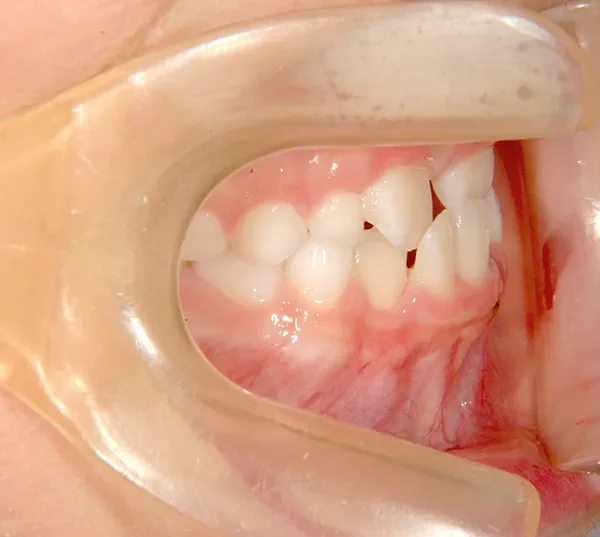

治療回数19回、2年5ヶ月の治療期間で矯正治療を終了しました。

主訴が改善され、ご満足頂きました。

治療終了後